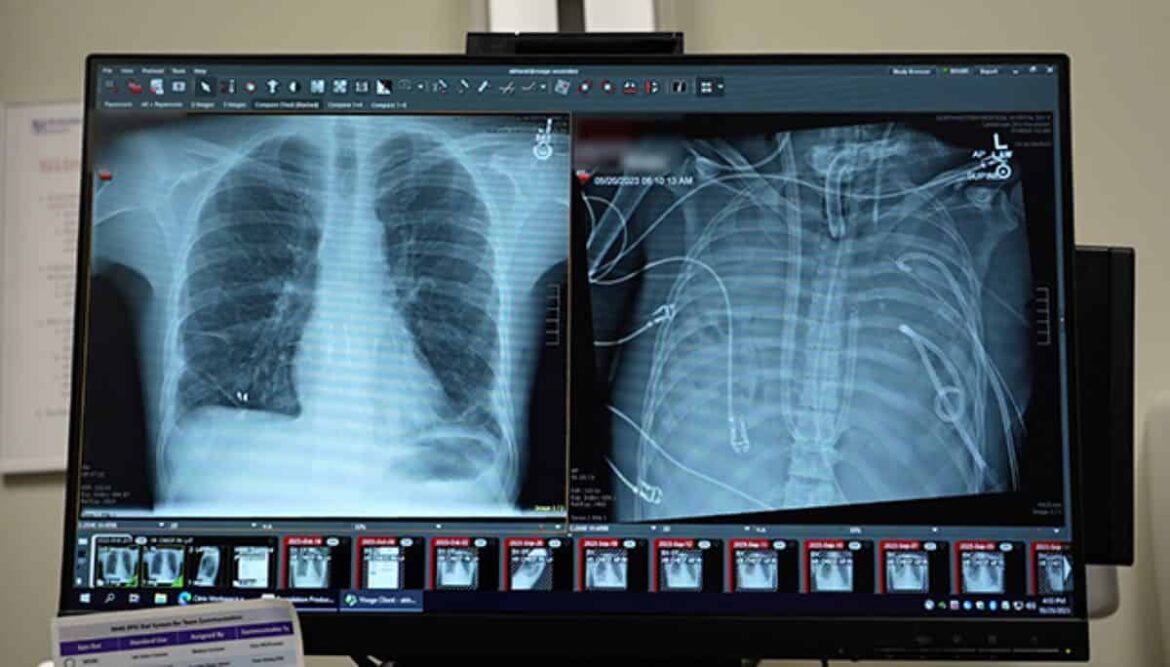

In the spring of 2023, a 33-year-old man arrived at Northwestern Memorial Hospital in Chicago with lungs that were rapidly shutting down. What started as a bout of influenza had spiraled into acute respiratory distress syndrome (ARDS). Then, a drug-resistant bacterial infection took hold.

Once the lungs were out, the doctors could finally examine the damage in detail. Using molecular and cellular analyses, the research team found evidence that the injury was irreversible.

The tissue showed widespread scarring and immune cell invasion. The cells that usually help regenerate lung tissue were largely absent. Instead, the lungs bore the molecular signatures of end-stage fibrotic disease.

For years, doctors have viewed ARDS as a condition from which lungs can recover if patients are supported long enough. This case offers biological evidence that, for some patients, recovery may never come.